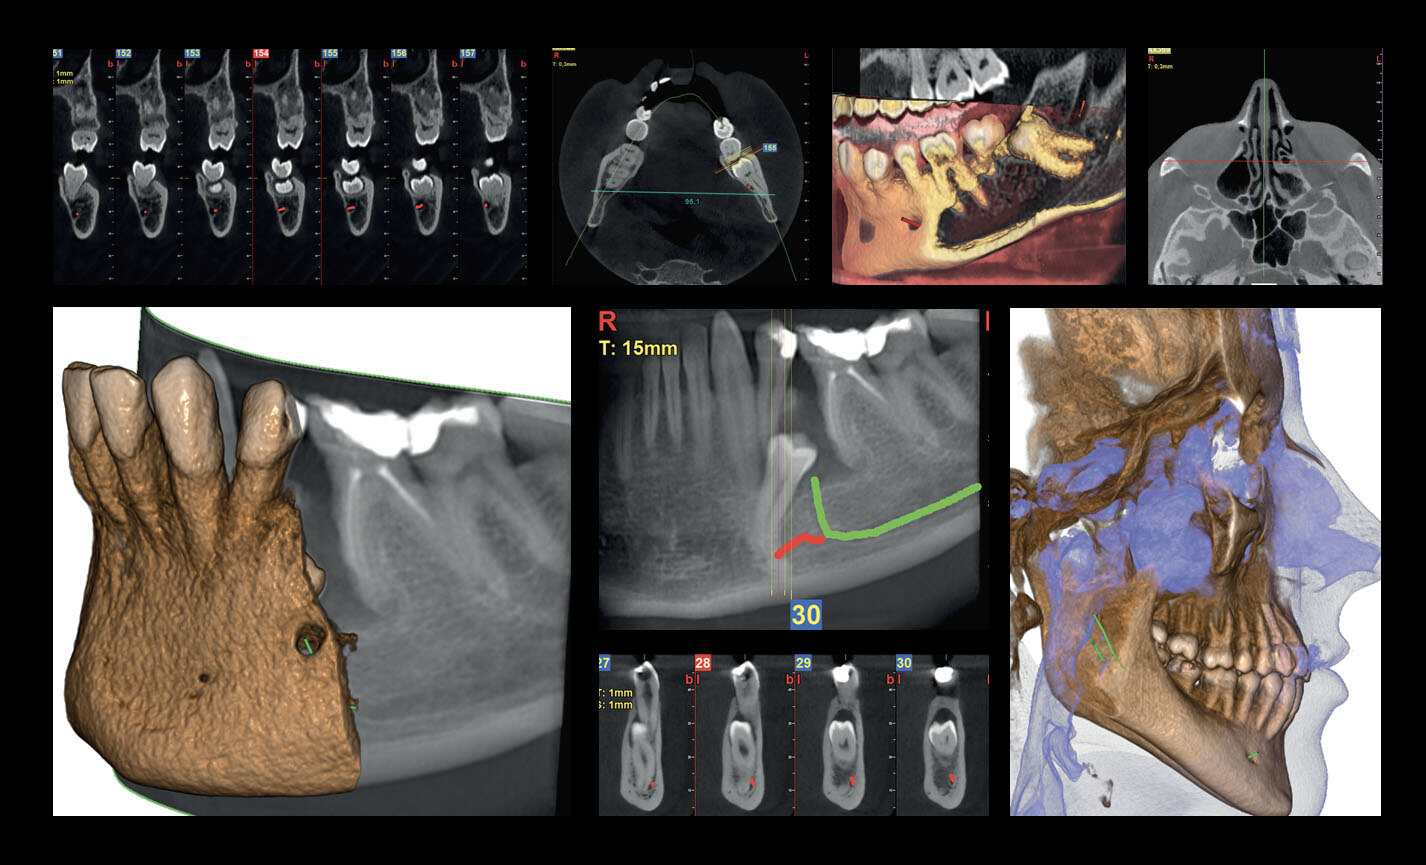

Des FOV de 10 cm de diamètre sont nécessaires pour l’étude des troisièmes molaires incluses car, chez un adulte de taille moyenne, la distance entre les troisièmes molaires de droite et de gauche, en incluant leurs racines respectives, le processus alvéolaire et l’os avoisinant, est d’au moins 9 cm. Les champs de vision réduits sont utiles en cas d’analyse de dents incluses ou surnuméraires, pour limiter la dose à la seule région d’intérêt. En effet, pour une planification correcte du traitement, il est fondamental de déterminer la position réelle (vestibulaire ou palatine), possible uniquement avec une analyse 3D, même à très faible dose avec un protocole QuickScan. Le champ de vision complet 13 x 16 cm permet une évaluation minutieuse des voies aériennes supérieures, souvent utile pour compléter une investigation en vue d’un traitement orthodontique qui tienne compte des problématiques oto-rhino-laryngologiques.

Planification implantaire avancée

Définissez la position de l’implant directement sur le modèle 3D, combinez-le avec les données STL provenant de scanners intra-oraux, et déterminez le projet prothétique définitif. Avec les instruments de planification implantaire avancée, vous pourrez opérer en toute sécurité, grâce aux informations précises sur la quantité d’os et la distance par rapport aux structures anatomiques avoisinantes, comme le canal mandibulaire, en définissant une distance minimale de sécurité.

Analyses volumétriques

La fonction du logiciel de calcul du volume de soulèvement du sinus maxillaire permet de déterminer l’intervention à l’avance et d’opérer en toute sécurité. Il est en outre possible de tracer des lignes directement sur le modèle virtuel du patient en évaluant les rapports morphologiques sur le rendu 3D.

Évaluation des implants zygomatiques

Les volumes avec FOV 13 x 8 cm, ou 13 x 10 cm, représentent l’outil idéal pour la planification des implants zygomatiques. En effet, le diamètre de 13 cm est le seul qui permet d’inclure tout le zygoma dans le balayage, sans coupes.